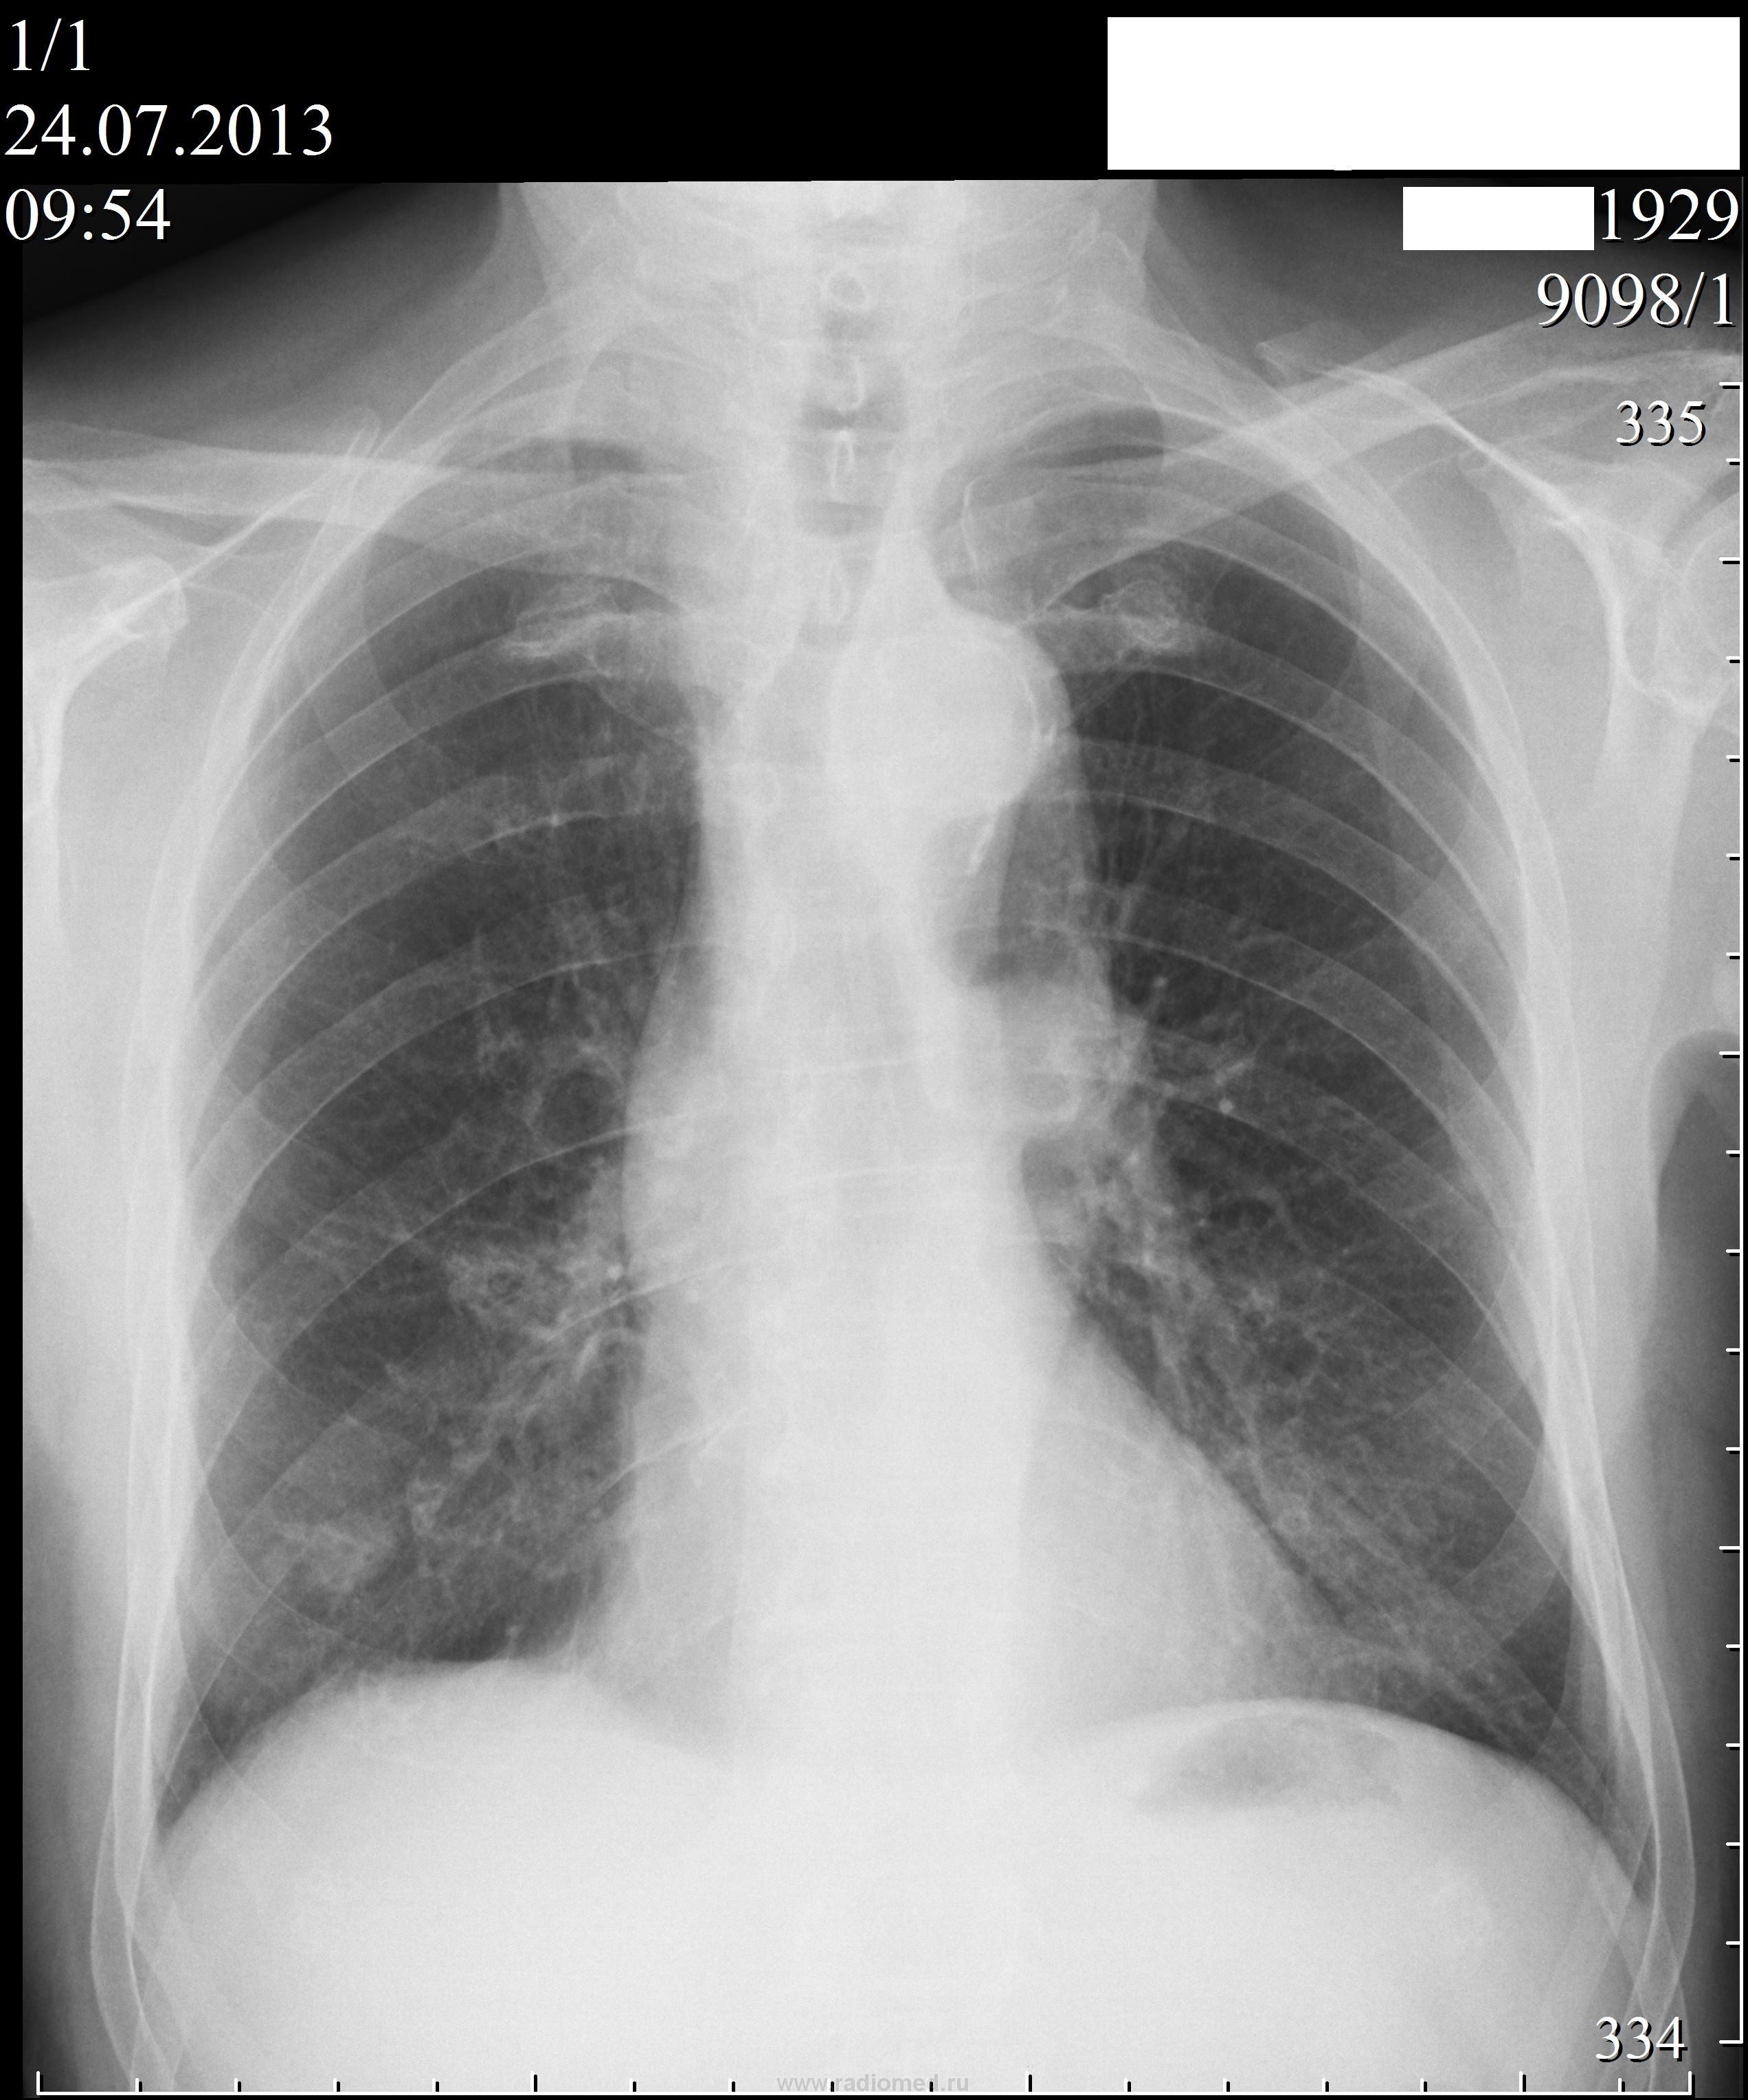

Синдром округлой тени.

Пациент 83 лет, проходил проверочную флюорографию лёгких. Жалоб не предъявляет.

Как можно расценить найденные изменения? Какой дифференциально-диагностический ряд можно предложить? Какова должна быть дальнейшая  тактика ведения пациента?

Тень среднеинтенсивная, овальная, с достаточно ровным и четким конткром, гомогенная. На фоне фиброза. Признаков злокачественности не вижу. Может и солитарный узловой мтс. А может ретенционная киста. Виктор Григорьевич, какие симптомы, кроме родной интуиции, сподвигли Вас указать на периферический?

1. Да, тень солитарная, но...

2. Локализация

3. Форма овальная

4. Контуры все таки волнистые,хоть и ровные

5. Тот же фоновый фиброз ?)...а почему собственно он, а не усиление легочного рисунка, что может быть при опухоли

6. Дорожка к корню

7. Всякая остальная мелочь

8. И ОНА, родная интуиция))))

Да, "круглая тень" есть.

Но, лично я, без линейных томограмм никаких выводов не делаю. В протоколе можно отметить круглую тень и рекомендовать линейку, или КТ.

Туберкулёмой, на мой взгляд, не пахнет

Без томографического обследования исключить туберкулёму нелзя.Внутренняя структура тени неоднородна,с мелкими просветлениями.Туберкулёма в дифряду обязательна.

Интересно было читать комментарии коллег! Ничего не зажимал и не припасал,  просто у меня на руках пока ничего больше нет. Дело в том, что родственники пациента, после выполнения R-графии лёгких в 2-проекциях, попросили распечатать им  эти снимки и флюорографический архив и пошли с ними в другую больницу, где была выполнена линейная томография и вынесено заключение о туберкуломе ( или по крайней мере, о процессе туберкулёзной этиологии, протокол пока не видел). По возможности, постараюсь разместить эти томограммы на сайте.  Фтизиатры, как я понял, согласились с таким заключением. Из тех версий, что выдвигалось на работе, но не прозвучали при обсуждении  на сайте, можно сказать о версии хондромы.

1.Периферический рак лёгкого.

2.Туберкулома (хотя в принципе, образование расположено ядноном слое лёкого, что нехаратерно для туберкулёза, при котором правило, процесс локализектся в плащевидном слое лёгкого).

3.Метастазы (есть рядом с округой тенью ещё одна, но меньших размеров).

4.Хондрома.

Однозначно показана КТ лёгких.

Пациенту выполено КТ лёгких.  Со слов сына вынесено заключение о раке лёгкого ( как я понял периферический рак лёгкого). Протокол КТ исследования и снимки должны принести  в течении нескольких дней. Пациенту назначена рентгенотерапия.